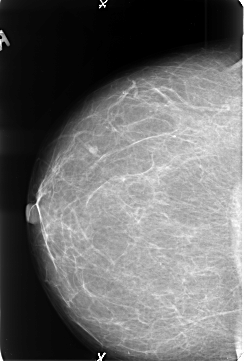

B_3478_1.LEFT_MLO

LEFT_CC LINES 4576 PIXELS_PER_LINE 3176 BITS_PER_PIXEL 12 RESOLUTION 50 OVERLAY

FILE: B_3478_1.LEFT_CC.OVERLAY

TOTAL_ABNORMALITIES 1

ABNORMALITY 1

LESION_TYPE MASS SHAPE IRREGULAR MARGINS CIRCUMSCRIBED-SPICULATED

ASSESSMENT 5

SUBTLETY 5

PATHOLOGY MALIGNANT

TOTAL_OUTLINES 1

BOUNDARY